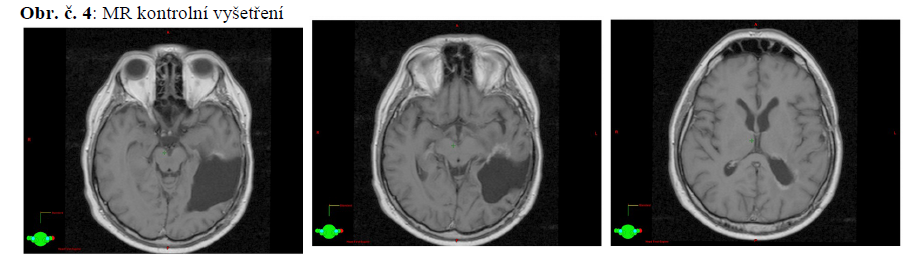

29.9.2010 MR mozku: pooperační reziduum neprokázáno, pooperační edém v okolí kavity, středočárové struktury téměř bez dislokace.

20.11.2011 MR mozku: bez známek tumoru CHT ukončena.

10.2.2014 MR mozku: stacionární nález rezidua tumoru vlevo temporálně při ventrálním okraji resekční dutiny.